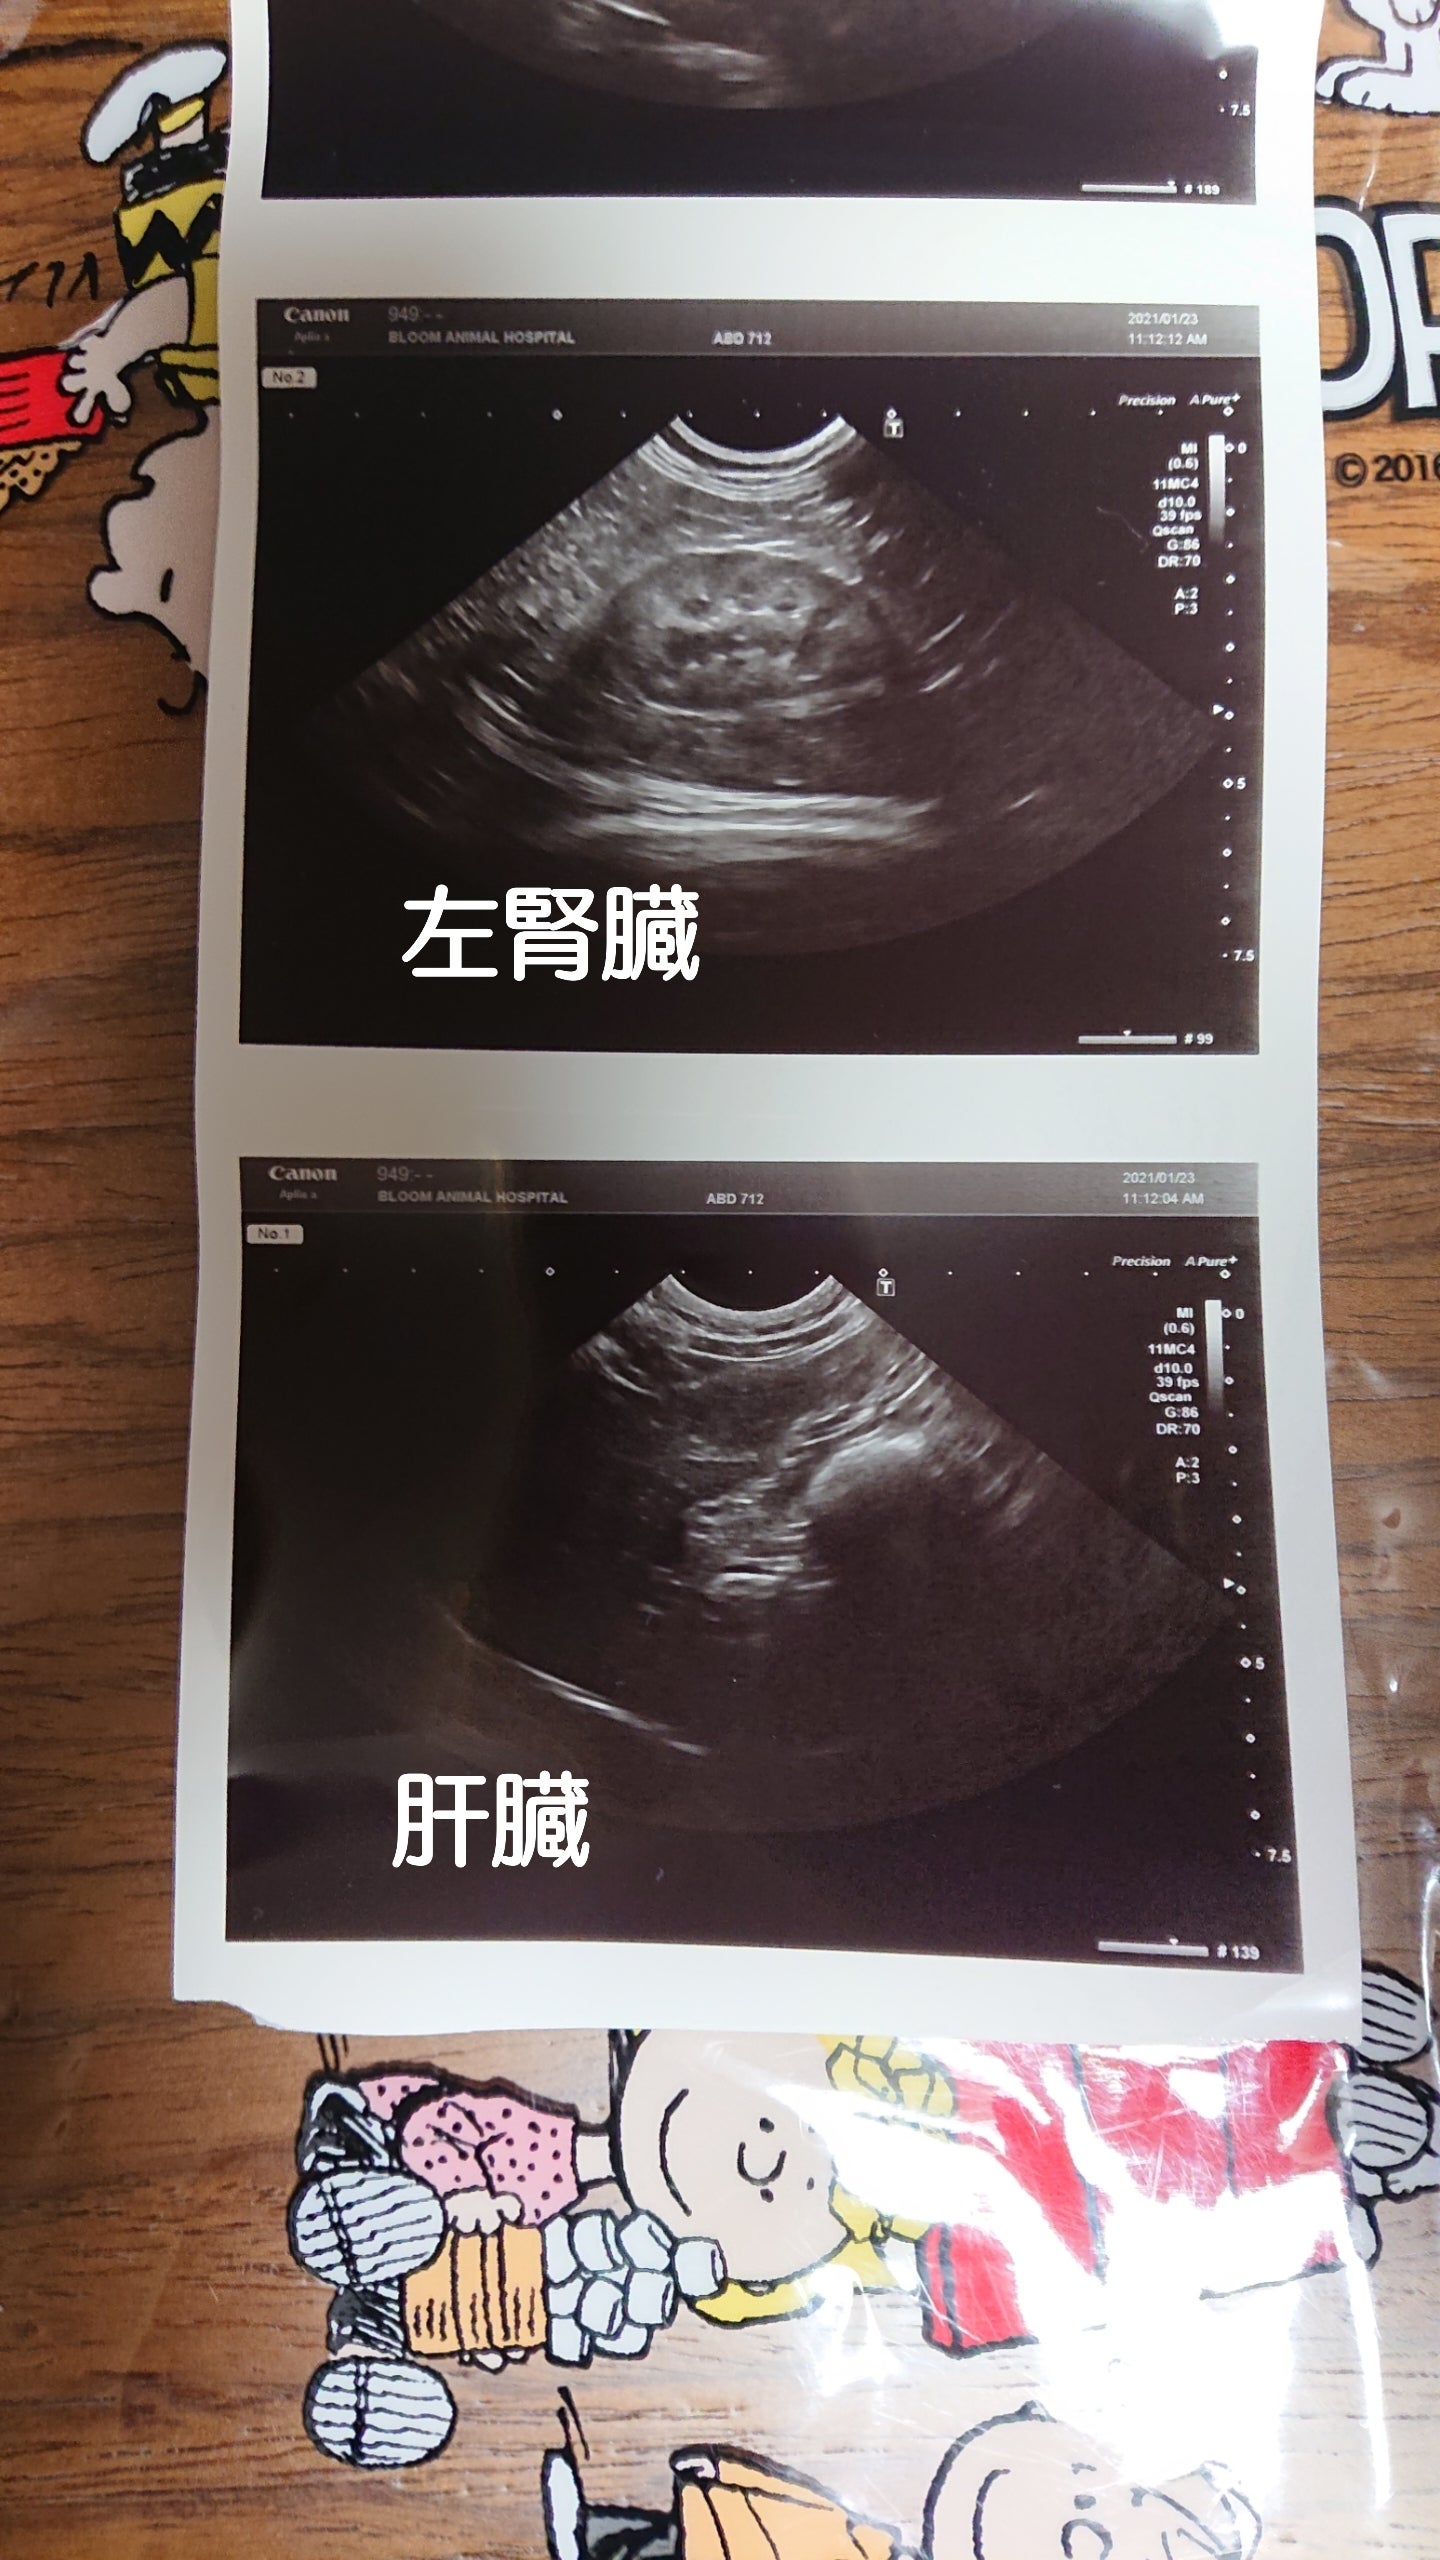

エコー

(初めてお写真いただきました。)

とても綺麗で異常なしです。